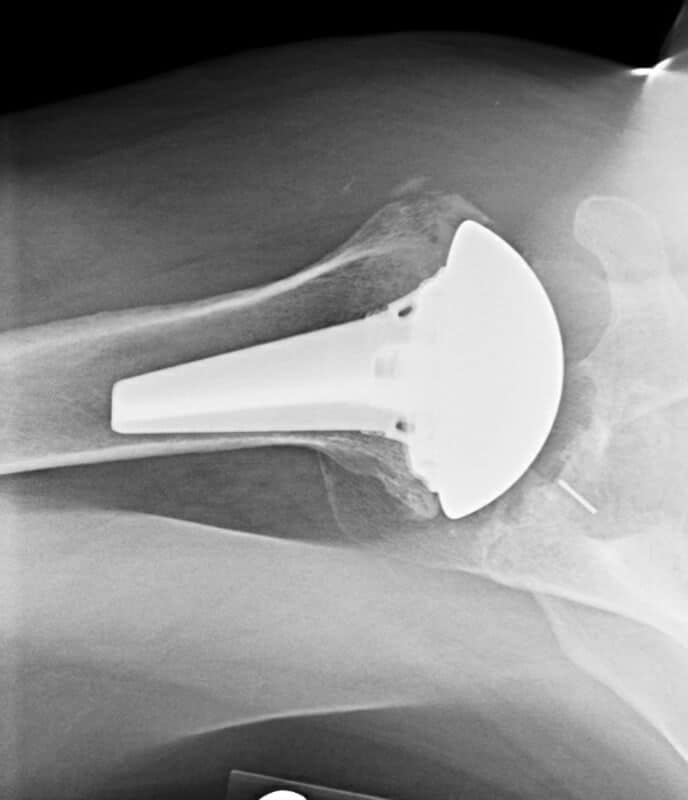

DePuy, Inhance